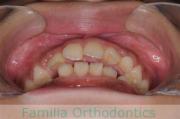

No.16V-202

- 主な症状:

- 叢生

- 年齢:

- 10歳

- 性別:

- 男性

- 抜歯部位

- 上:

- 44

- 下:

- 4|3

- 主な使用装置:

- FEA

- 治療にかかった費用:

- 92万円

歯並びを治したいということで小学生のときに来院されました。二期治療で小臼歯抜歯の可能性が高いと判断しましたが、スペースの不足が著しいため、上下を拡大してから成長観察に移行しました。

左下犬歯に異常があったので、この歯と左右上&右下の小臼歯を抜歯してマルチブラケットを行いました。約4年、30回以上の通院が必要でした。

左下犬歯の形成異常は原因がわかりませんでした。犬歯は寿命の長い大事な歯なので、抜くことにはリスクがありますが、本ケースではやむを得ない判断だったと思います。